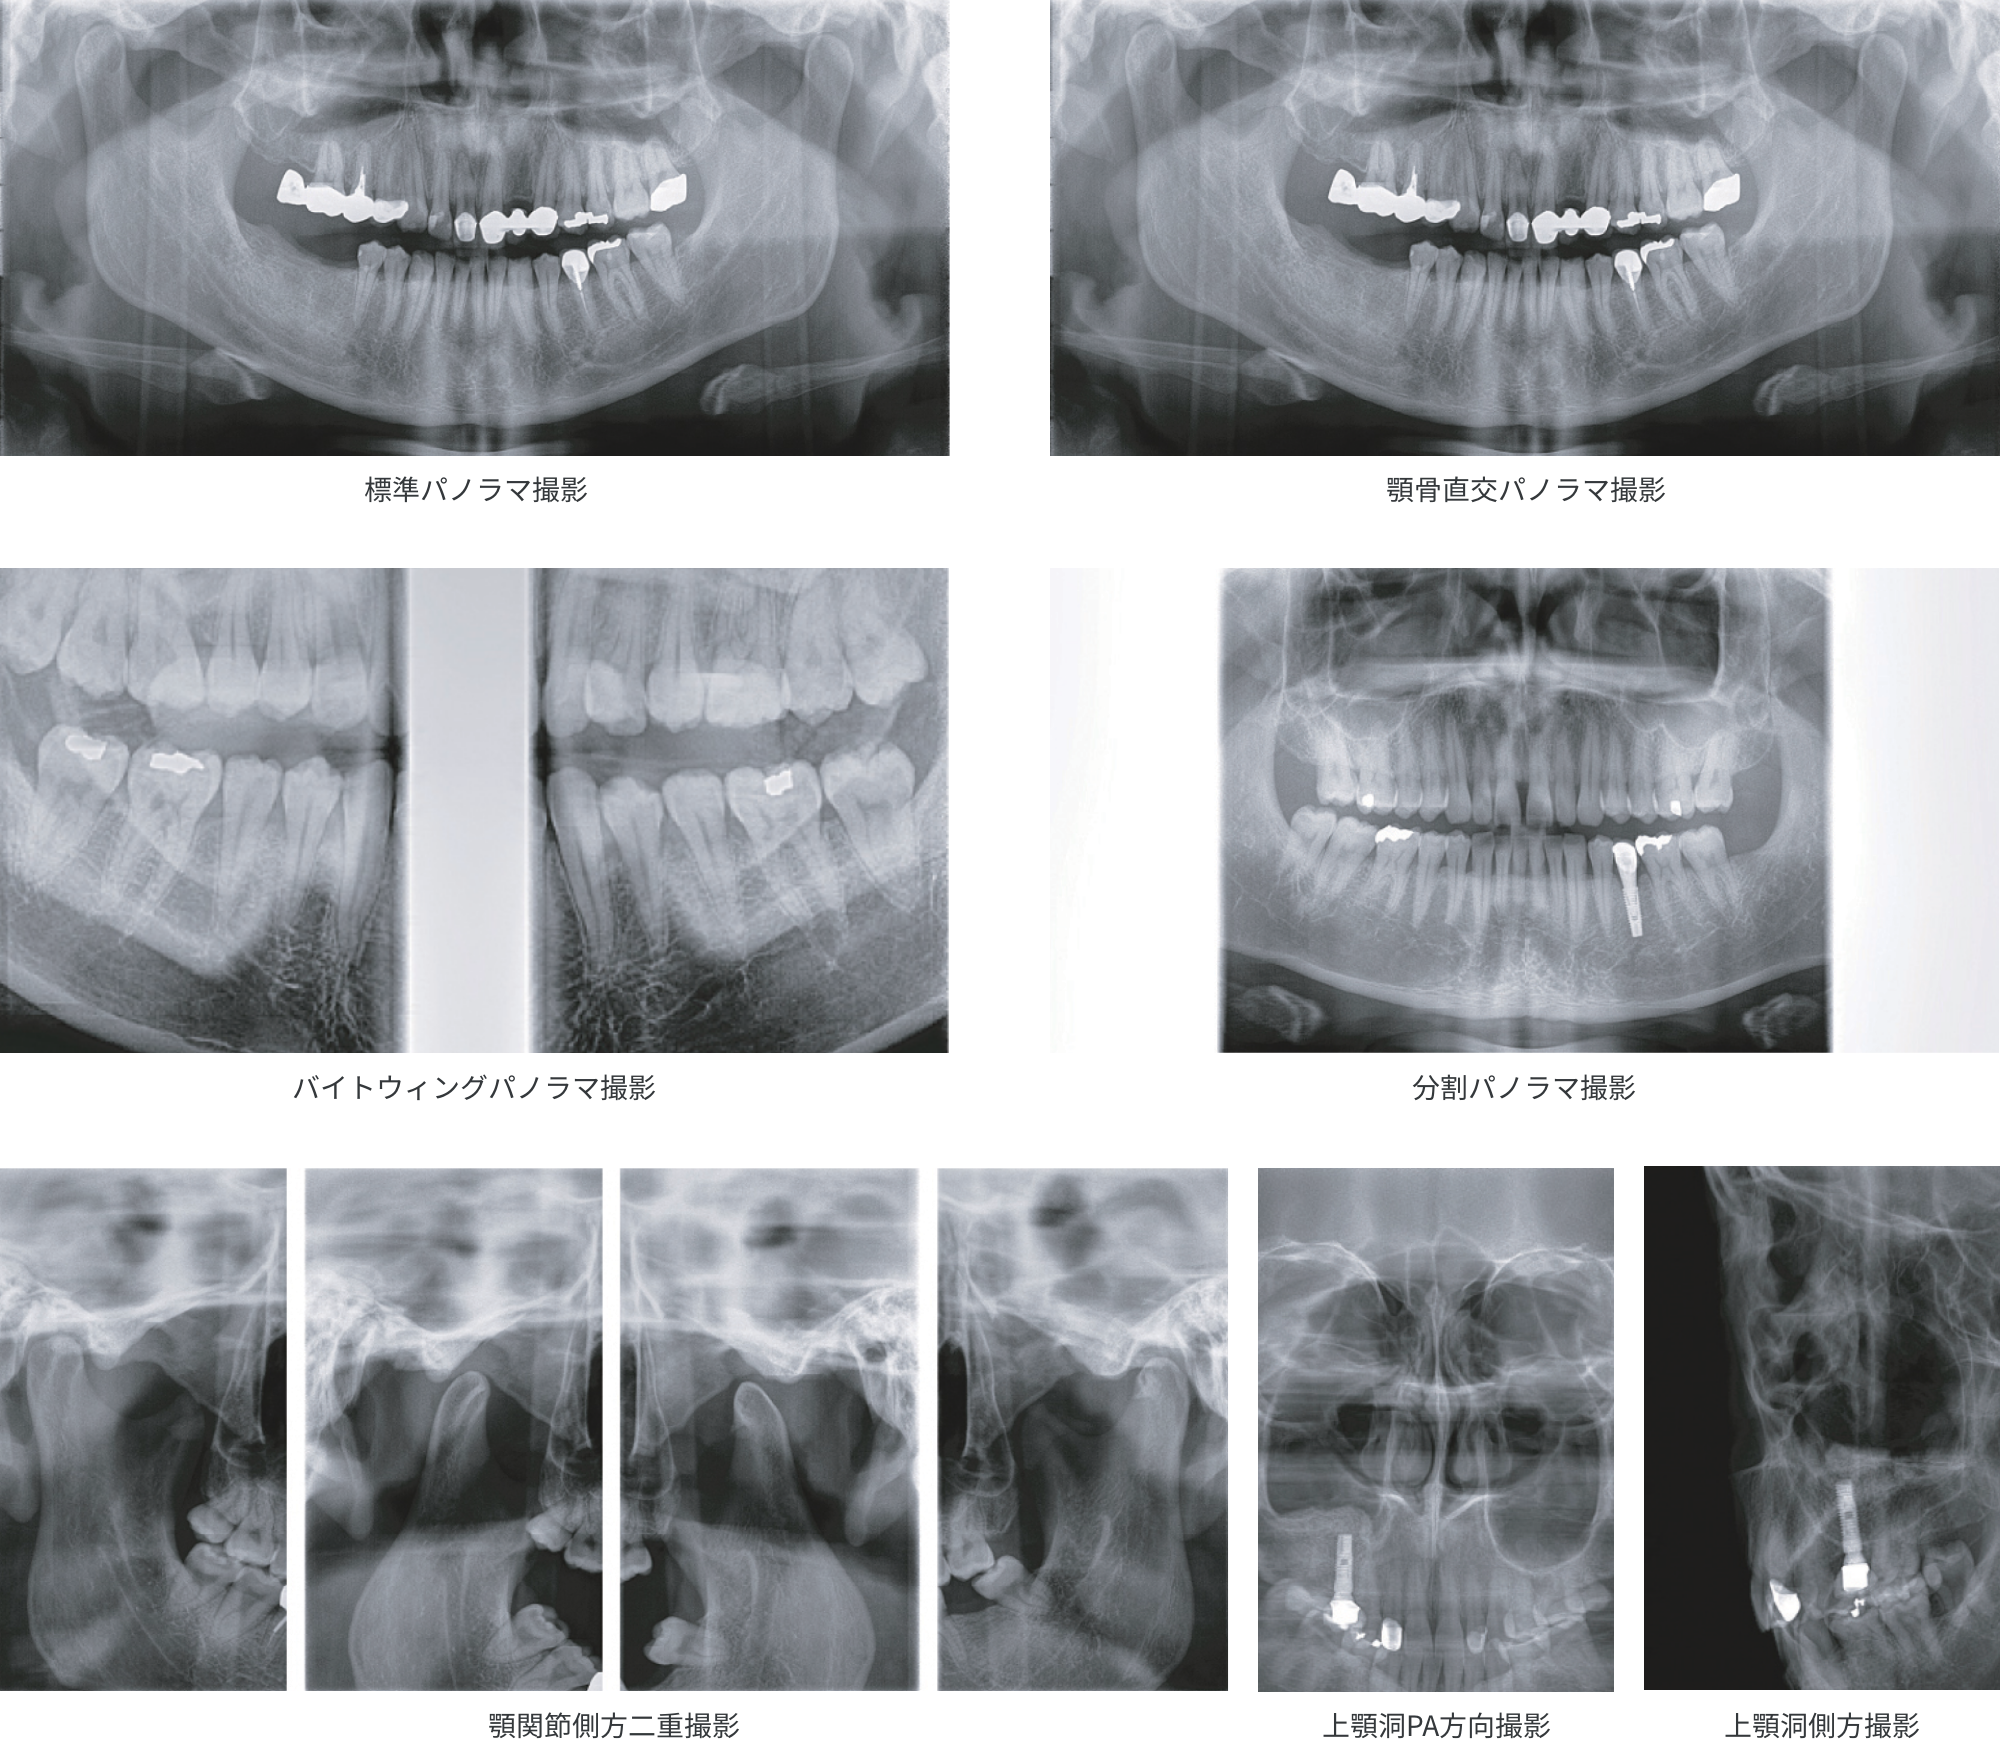

Aadva GX-100 3Dは、最新の3in1(CBCT、パノラマ、セファロ)X線撮影装置です。

ST仕様、MX仕様の2つのモデルから目的に合った装置を選択いただけます。

エンド、ペリオなどの日常臨床からインプラント治療や矯正治療などの様々な

歯科治療において正確で詳細な診断画像を提供します。

「オートフォーカス」はパノラマモード専用の機能です。焦点が合う最適な部分を自動で抽出して画像を生成します。位置付けの失敗による再撮影のリスクも軽減されます。

撮影モードは、Fast、Normal、HD(High-Definition)の3段階から画質を選択することができます。